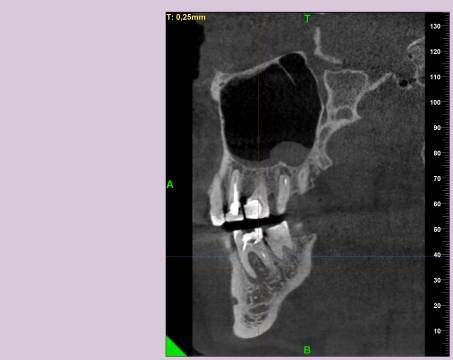

КТ от 28.05.2024

28_05.24(2).jpg.0ffa1febe861106733e1de830afbe6f4.jpg28_05.24-1(2).jpg.9c45d7be16aeed505bd413ce9bc6e69e.jpg28_05.24-2.jpg.a728a7d7e6213c1c8302b43adc89e4d0.jpg28_05.24-4(2).jpg.ac43f3448a3988c7006f74e1d0ce09da.jpg28_05.24-6(2).jpg.dd1fd85c6cc0fcd3d43bd9e71fc0d616.jpg28_05.24-8(2).jpg.885c8cb905445e9308f124fb9e5c616b.jpg28_05.24-9(2).jpg.6cceaaaa1b56d0967482c87b951fbe2d.jpg28.5.24-5(2).jpg.b2d79427a16769c9fd4f0d0911a9db8f.jpg28.5.24-7(2).jpg.f6c17f9820e72dc2708955a65a190b57.jpg28.0524-3(2).jpg.0aa9f153071766a340b428158a94ade8.jpg

Лекарство было извлечено, и каналы запломбированы гуттаперчей. Доктор предупредила, что зуб будет болеть, и прийти я должен после того, как зуб "успокоится", болевые ощущения пропадут. На третий день десна под зубом вспухла, и начала сочиться сукровица. Я решил сделать новое КТ(28.05.2024), и с результатом сходить в другие клиники для консультации. В первой мне сказали, что доктор не должна была начинать лечение, потому, что зуб идет под удаление. Во второй клинике, что попытаться вылечить можно, но изначально были допущены ошибки в лечении, и надо переделывать.

Что-то можно сделать с 46 зубом для сохранения, или он должен быть удален?